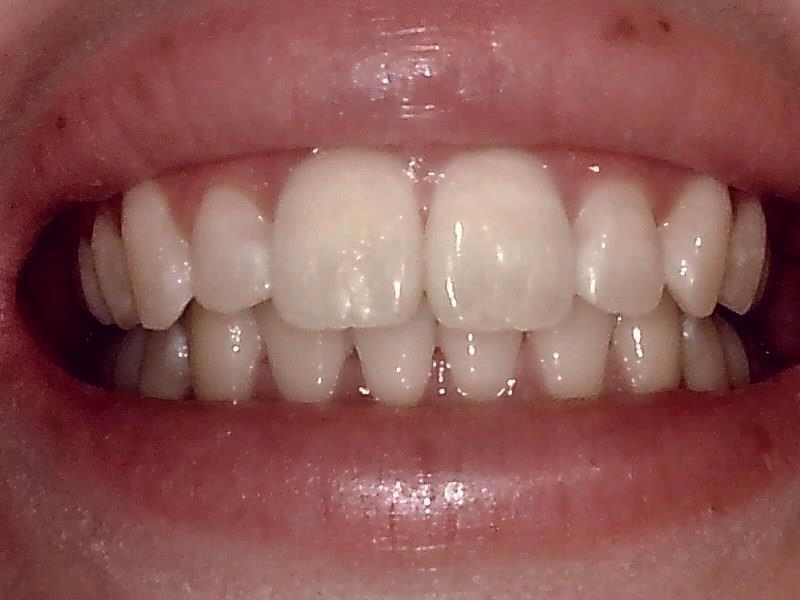

術前口腔内写真 正面観

術後の口腔内写真 正面観